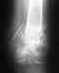

Помогите советомМне 30 лет.В декабре на производстве я сломалбедро, перелом диафиза. сделали операцию, загналидлинный стержень и 4 болта по краям.

после операции прошло 2 месяца уже хожу домабез костылей.Меня мучает вопрос смогу ли я как раньше прыгать с высоты или я уже отпрыгался?будет ли мне мешать фиксатор или из за него еще где нибудь сломается? может его потом удалитьдля надёжности?

Как Вы "раньше прыгали с высоты" - остатеся только гадать. В принципе, при восстановлении длины, оси и ротации конечности после сращения вполне ожидаемо полное восстановление возможностей до уровня перед травмой. Фиксатор такого типа мешает, только если его элементы сильно выстоят из кости в окружающие ткани, тогда его следует убрать. Бессимптомные такие фиксаторы убирать необходимости нет.